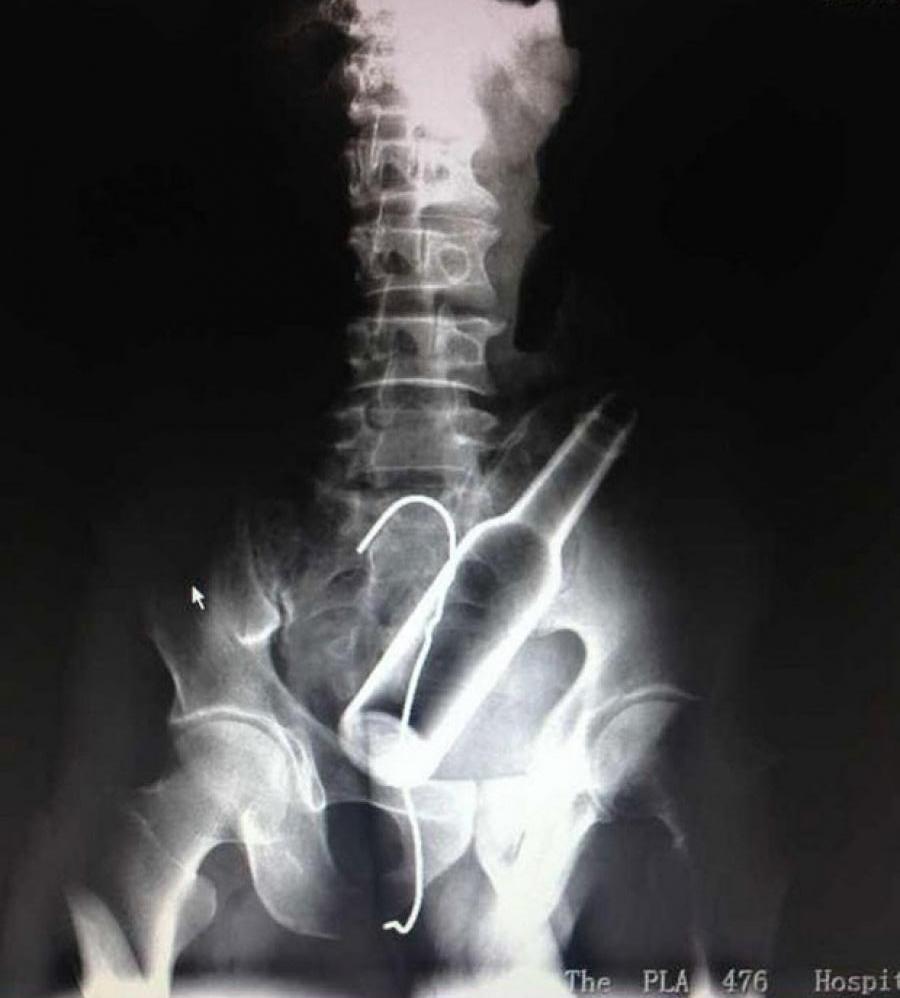

Por mais bizarra que pareça essa história ela é 100% real. O chines ao chegar ao hospital, os médicos perceberam que o paciente estava relutante em contar o que havia acontecido e, após um exame de raio-X, identificaram uma garrafa no reto do homem, junto a um pedaço de arame.

O homem acabou confessando que inseriu a garrafa no ânus por conta própria, mas não conseguiu removê-la. Em pânico, tentou usar um pedaço de arame para “fisgá-la”, e também não obteve êxito.

Foi necessária uma operação para remover os objetos do corpo do chinês, além de reparar pequenos ferimentos na bexiga causados pelo arame.